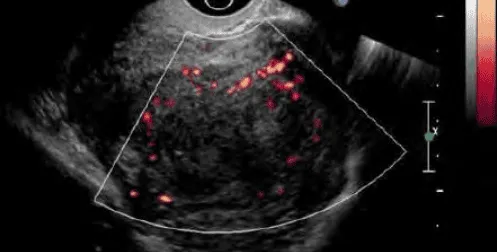

Doppler: Mạch ngoại vi u xơ; Phân biệt với polyp (mạch trung tâm) và adenomyosis (mạch nội vi).

Hình ảnh “U xơ tử cung trên siêu âm Doppler”.